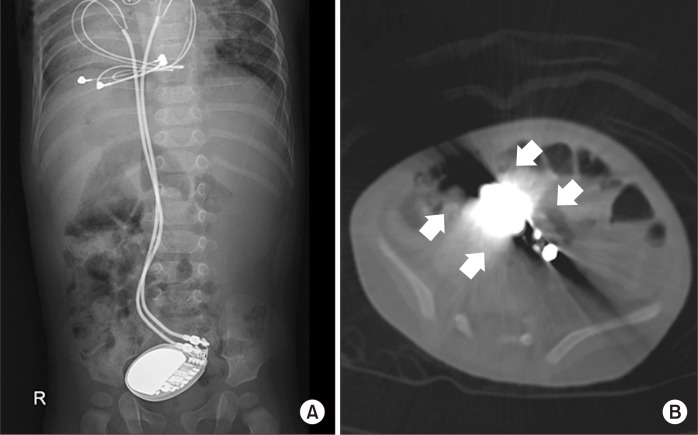

A Case Report of Rare Complications after Epicardial Permanent Pacemaker Implantation in an Infant: Airway Compression, Skin Necrosis, and Bowel Perforation.

Insertion of an epicardial pacemaker is a useful treatment for pediatric patients with an abnormal heart rhythm. However, there are limitations and concerns when implanting epicardial pacemakers in infants and neonates due to their small body size. We report a patient who experienced rare complications after implantation of a permanent pacemaker.